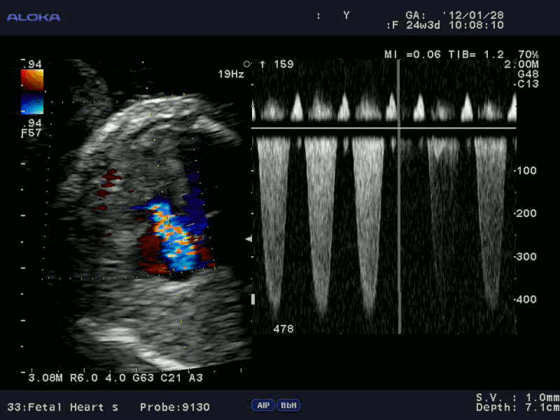

Эходопплеркардиография — это инструментальный метод исследования сердца и кровеносных сосудов, при котором применяются ультразвуковые технологии. Как и при «рутинных» (М-режимной и двухмерной) эхокардиографиях (ЭхоКГ), данная методика использует высокочастотные звуковые волны, чтобы создать изображение сердца. Но помимо этого, чтобы определить скорость и направление кровотока, она дополняется эффектом Допплера.

Основные режимы визуализации, применяемые при УЗИ сердца

Ультразвуковое исследование сердца в основном используется для получения двухмерного изображения этого органа и близлежащих магистральных сосудов. А также с помощью этой методики можно оценить скорость и направление кровотока, что требует применение эффекта Допплера. В зависимости от того, как обрабатывается и отображается на мониторе эхо-сигнал, различают следующие режимы ЭхоКГ:

- Двухмерный (2D режим). На монитор выводится изображение сердца в разрезе (в двух измерениях). Данный способ является основным при визуализации этого органа, позволяет детально рассмотреть анатомические отклонения и аномальные движения миокарда, клапанов.

- М-режим (M-mode). Это «усеченный» вариант предыдущего, при котором используется для анализа только одномерное изображение. Основное внимание уделяется одной из линий 2D трассировки, что позволяет более детально исследовать движения створок клапанов и сердечной мышцы.

Для облегчения выявления турбулентного движения (завихрений) существует порог скорости, выше которого происходит изменение цвета (во многих аппаратах это зелены). «Мозаичный» узор на участке турбулентного потока позволяет легко установить регургитацию (смену направления движения), что помогает определить степень недостаточности клапанов.